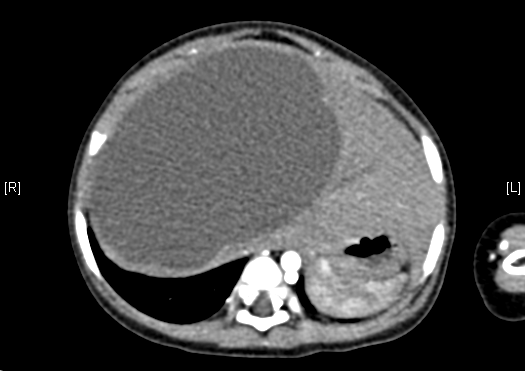

上腹部增强CT:肝右叶囊实性占位。上腹部增强CT示间叶性错构瘤。

术前CT检查:

动脉期

静脉期

平衡期